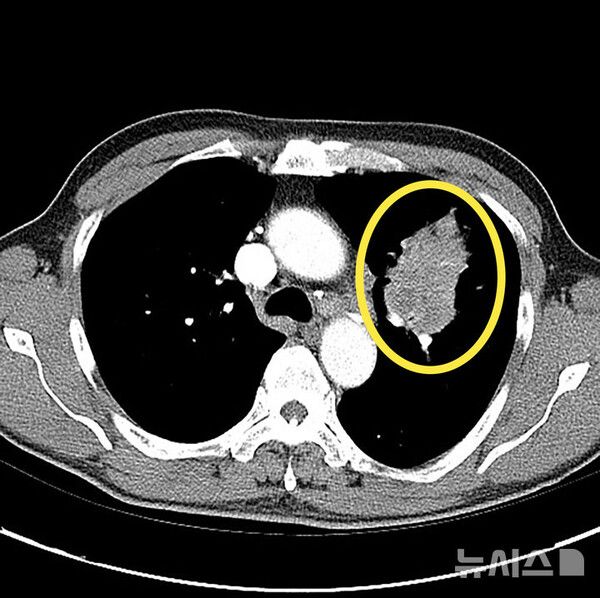

사진 = 뉴시스

폐암은 초기 증상이 없는 경우가 대부분이고, 일반 감기와 증상이 비슷해 진단이 늦어지는 경우가 많다. 건강검진에서 우연히 결절이 발견돼 추가 검진을 통해 진단 되곤 한다.

15일 의료계에 따르면 폐암은 폐에 비정상적인 암세포가 무절제하게 증식해 종괴(덩어리)를 형성하고 인체에 해를 미치는 것을 말한다. 폐암은 폐에 국한돼 발견되기도 하지만 진행될 경우 반대쪽 폐뿐 아니라 임파선이나 혈액을 통하여 뼈, 간, 부신, 신장, 뇌, 척수 등 온몸으로 전이될 수 있다.

하지만, 최근에는 비흡연자에게서도 폐암 발병이 증가하고 있어 증상이 없고 고위험군이 아니더라도 관심을 기울일 필요가 있다. 간접흡연이나 요리시 발생하는 연기, 라돈·석면 등 발암물질에 노출되는 직업 종사자나 미세먼지 노출시에도 폐암에 걸릴 수 있다. 저선량 흉부 CT(컴퓨터단층촬영)는 폐암 조기 진단에 매우 효과적인 수단으로 만성 폐쇄성 폐질환(CODP)이나 다른 암 병력이 있는 등 고위험군에서는 정기적인 검사가 권장된다. 저선량 CT는 환자에게 노출되는 방사선량을 6분의 1 수준으로 최소화한 장비다.

따라서 고위험군에서는 저선량 CT를 이용한 정기 검진이 매우 중요하다. 결절이 발견된다고 다 암으로 진행되는 것은 아니다. 결절은 암일 수도 있지만 염증, 섬유화, 림프절 비대, 과거 결핵 흔적 등 다양한 원인으로 생길 수 있다. 특히 폐암 고위험군이라면 호흡기알레르기내과 전문의에게 진료를 받아 정확한 평가를 받는 것이 필요하다.